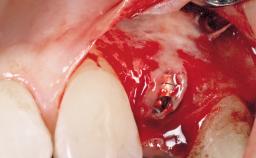

Late Flapless Placement of an Implant in a Maxillary Left Central Incisor Site

A 39-year-old male patient presented with a chief complaint of discomfort and gingival discoloration around his maxillary left central incisor. He was in good general health and was a non-smoker. His past dental history was significant because of the traumatic fracture of tooth 21 in a sporting accident at age 13. Initial dental treatment included endodontic therapy and a full-coverage restoration. The patient became symptomatic 5 years later, when structural failure of the tooth resulted in the dislodgment of the crown. Endodontic retreatment, apical surgery, and post-and-core restoration were performed.

| Soft Tissue Grafting | Simultaneous |